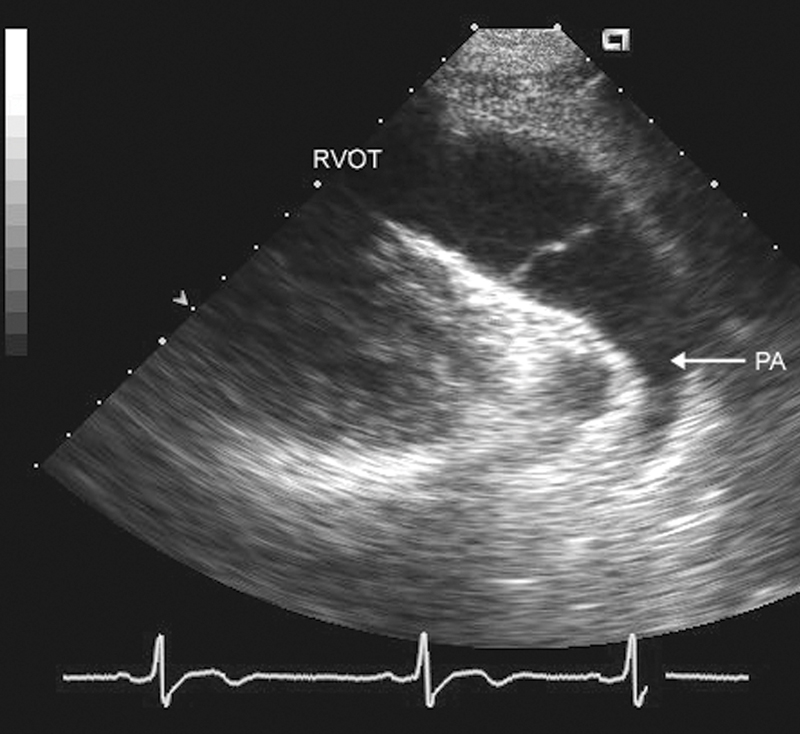

فحوصات تشخيصية لبعض امراض القلب والشرايين التاجية